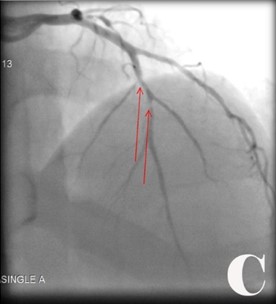

Fig. Abordaje invasivo emergente en paciente con Angina inestable de Alto riesgo y cambios electrocardiográficos atípicos con FEVI muy baja.

Fig. Se visualizó obstrucciones largas proximal y distal de 90 % de coronaria derecha (CD) (2A). Se realizó ACTPs y coloco 2 Stens convencionales (2B). Obstrucción de tercio proximal de 90 % de arteria coronaria de descendente anterior (DA) y del 95 % de la circunfleja izquierda (CX) (2C), se le realizó ACTP y colocó Stens a la DA fármacoactivo pero por el riego-beneficio se decidió no hacer nada en CX (2D).